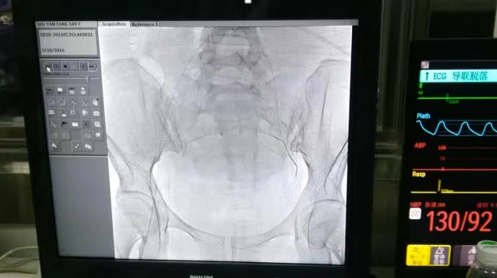

产后出血,是分娩期的严重并发症,居我国产妇死亡原因首位。一场极速生死大营救迅速展开: 上呼吸机、持续心电监护;补液、输血;配血化验;球囊压迫宫腔等,防肾衰、心衰以及失血性休克及DIC……在经过一系列的抢救措施后,产妇仍然面色苍白、心率加快,血氧饱和度低,同时出现阴道大量凝血块,出血量已超过全身总血量的3/4,如果再不能有效止血,产妇将面临切除子宫,甚至死亡的风险……抢救的医护人员决定对产妇在输血的同时,行双侧髂内动脉栓塞术,这是我院首例成功运用介入技术救治产后出血的病例。经过9个小时的惊心动魄的“战斗”,晚上18时许,产妇阴道流血被有效控制,各项生命指标逐渐恢复到正常水平。